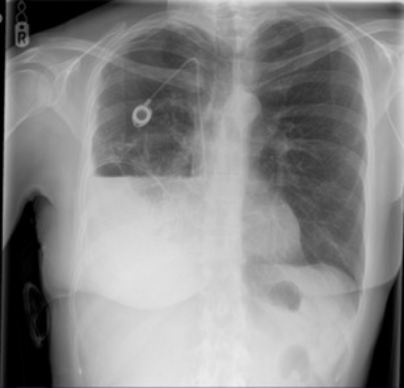

Chest x-ray post-IPC placement with right hydropneumothorax with partial lung entrapment3

3. Prof Mohammed Munavvar. Clinical image taken with patient’s consent.